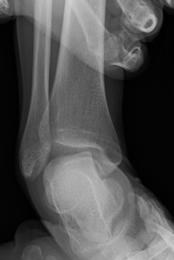

慢性足関節外側靭帯損傷

足関節の外側靭帯は、足関節の内返しの捻挫で最も損傷しやすい靭帯です。捻挫に対して適切な治療がなされなかったり、捻挫を繰り返したりすることで、慢性の外側靭帯の機能不全に陥ることが少なくありません。その場合、運動時の足関節の不安定感や疼痛、腫脹を生じます。

まず当院では、リハビリテーションによる回復を望めると判断した場合は、リハビリテーションによる保存的治療を行います。保存的に治療を行っても痛みが残る場合には、外側靱帯の縫縮術等を行っています。外側靱帯損傷に伴った軟骨の損傷を確認し、また手術における組織への侵襲を減らすため、可能な限り関節鏡で縫縮を行っています。損傷がひどい場合には再建術を行うこともあります。

![]() 内反ストレス単純レントゲン写真 |

![]() 関節鏡視下靭帯縫合手術 |